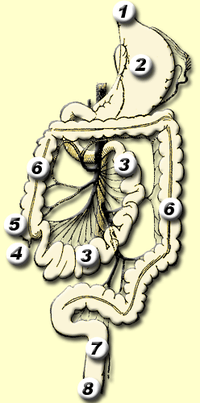

The human digestive system consists of the gastrointestinal tract plus the accessory organs of digestion (the tongue, salivary glands, pancreas, liver, and gallbladder).[1] In this system, the process of digestion has many stages, the first of which starts in the mouth. Digestion involves the breakdown of food into smaller and smaller components, until they can be absorbed and assimilated into the body.

Components

There are several organs and other components involved in the digestion of food. The organs known as the accessory digestive glands are the liver, gall bladder and pancreas. Other components include the mouth, salivary glands, tongue, teeth and epiglottis.

The largest structure of the digestive system is the gastrointestinal tract (GI tract). This starts at the mouth and ends at the anus, covering a distance of about nine (9) metres.[2]

The largest part of the GI tract is the colon or large intestine. Water is absorbed here and remaining waste matter is stored prior to defecation.[1]

Most of the digestion of food takes place in the small intestine.

A major digestive organ is the stomach. Within its mucosa are millions of embedded gastric glands. Their secretions are vital to the functioning of the organ.

Lower gastrointestinal tract

The lower gastrointestinal tract (GI), includes the small intestine and all of the large intestine.[29] The intestine is also called the bowel or the gut. The lower GI starts at the pyloric sphincter of the stomach and finishes at the anus. The small intestine is subdivided into the duodenum, the jejunum and the ileum. The cecum marks the division between the small and large intestine. The large intestine includes the rectum and anal canal.[1]